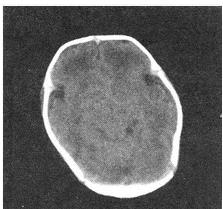

- 单项选择题 患者女性,15天,吸允反射减弱,CT检查如图,最可能的诊断为()。

D、新生儿缺氧缺血性脑病

- D